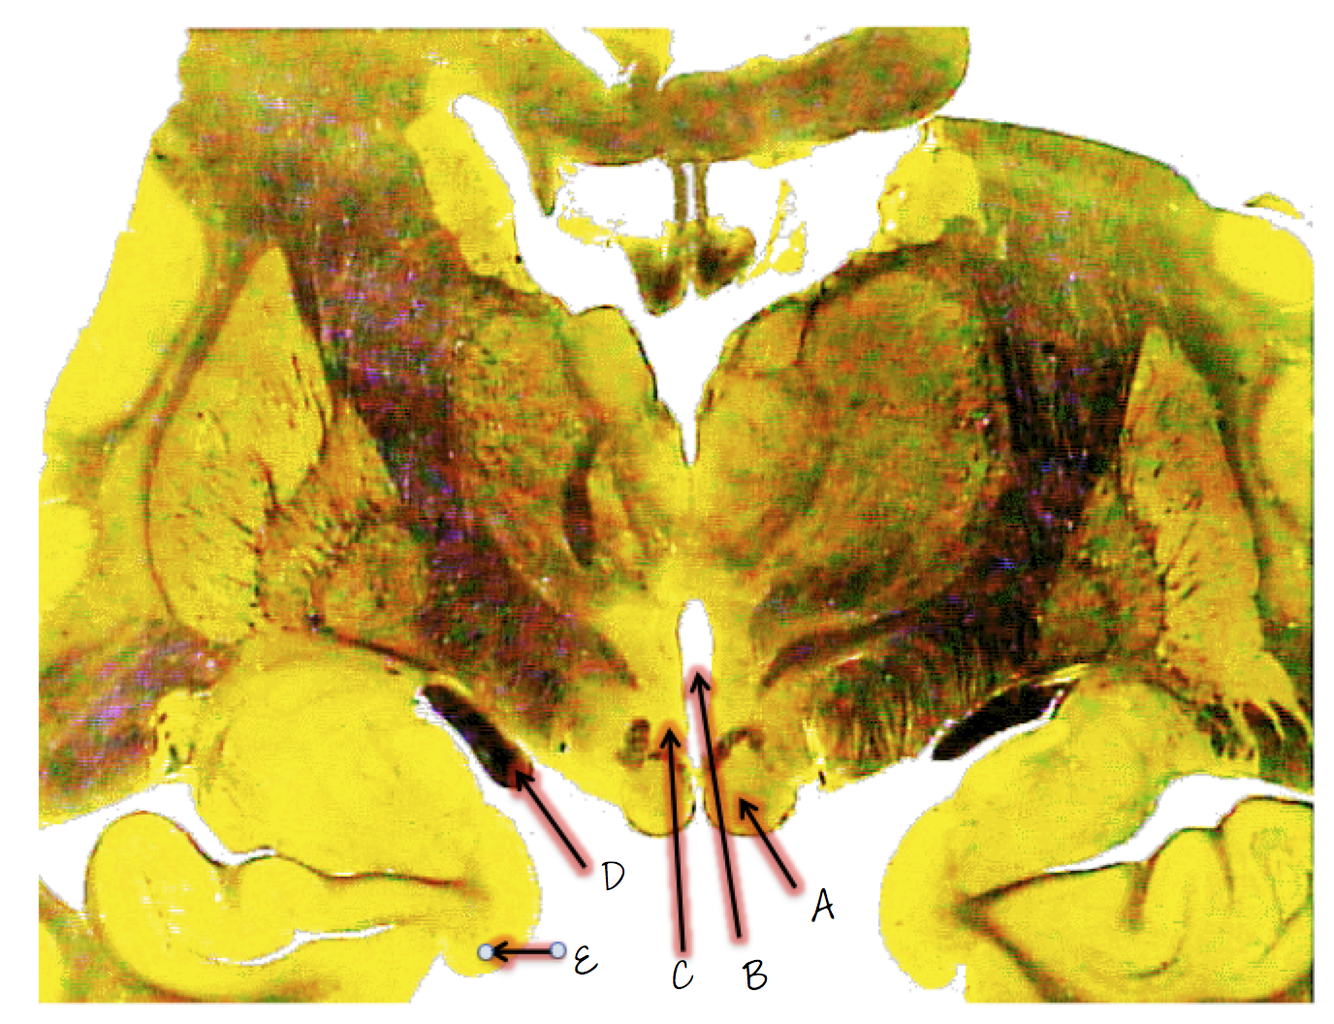

A; mammillary body

B; third ventricle

C; hypothalamus

D; optic tract

E; uncus